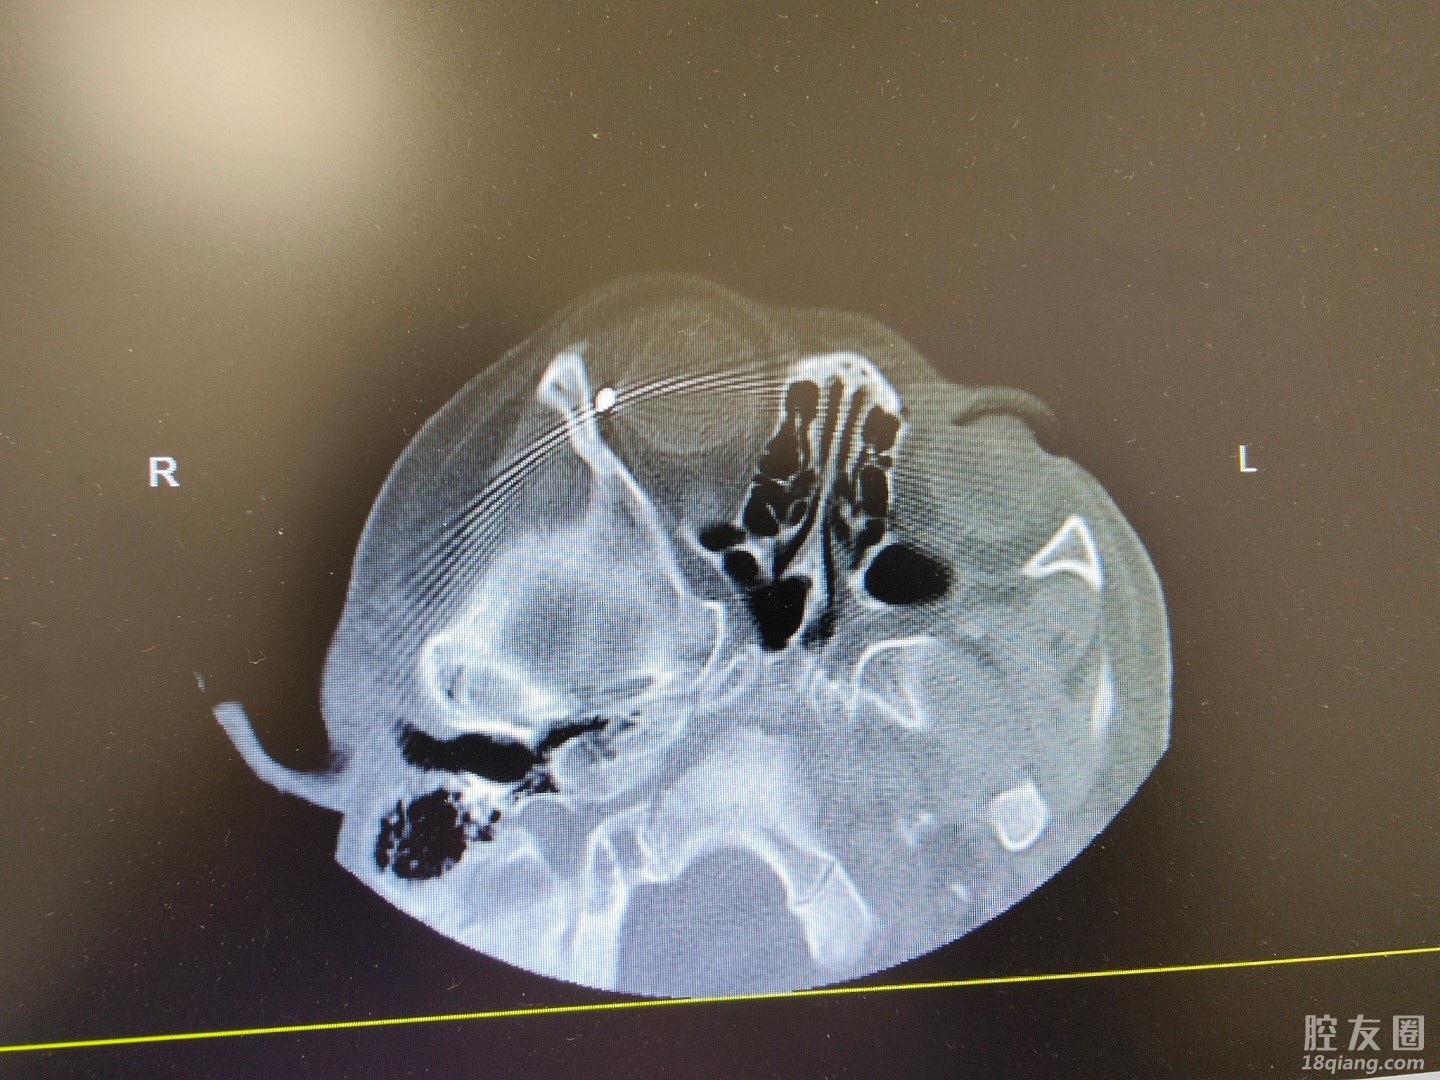

“马上进行眼眶CT扫描,确认患者有无伤到眼球,如果伤到眼球,那插入的笔尖切不可贸然拔出。”不到5分钟,医生就已达到急诊,并根据患者情况,开始针对性检查。

眼睛对于一个小女孩来说,是至关重要的,如果笔尖刺入眼球,那必然对其视力造成不可逆的伤害。但万幸的是,通过CT检查,发现笔尖虽然刺入眼眶内,但仅仅毫米之差,停留在了眼眶的外侧壁,并没有刺中眼球,随后在局麻下小心地为其将笔取出。

“这个孩子,真的太幸运了!初步检查,视力并没有受到影响,眼眶CT复查也可以排除眼球裂伤的可能。”第二天下午,眼科主任张美对其进行全方位检查后,高兴地说道。